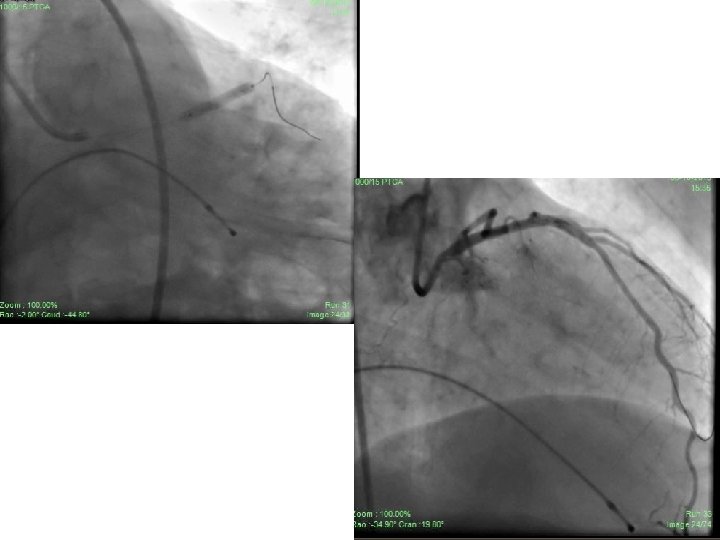

• Patient was taken up for PCI to RCA and LAD through RFA access under TPI. • RCA hooked initially with JR 3. 5/6 F guiding catheter then AL 1/6 F guiding catheter. • Lesion finally crossed with Miracle-3 wire using balloon support. • Lesion dilated with 1. 25 X 8 mm CTO balloon and 2. 0 X 15 mm Sprinter Legend balloon. • Xience-V 2. 75 X 28 mm stent deployed successfully in distal RCA with normal flow through and beyond stent. • TIMI – III flow achieved. • 50% residual stenosis remained distal to stent at crux and PLV.

• In the same sitting, bifurcation lesion in LAD was tackled. • Using JL 3. 5/6 F guiding catheter, lesion crossed with BMW guide wire in LAD (D 1 could not be entered in spite of repeated attempts). • Angioplasty to LAD done with 2. 0 X 15 mm S. L. balloon. • Xience-V, 2. 75 X 23 mm was deployed in LAD. • D 1 was pinched with TIMI – I flow though there was normal flow through and beyond stent in LAD with TIMI –III flow. • Intra- coronary bolus and i. v. infusion of Tirofiban was used. • Patient was pain free and no ECG changes were seen. • Discharged on day 3 from hospital and continued on conventional anti anginal therapy.